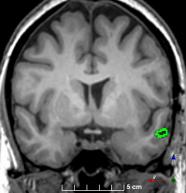

Figure 3: Manual labels from Rater A (green) and Rater D, the model trained with PubFull + EpiPre + Pseudo (magenta). Errors caused by a (a) small resection, (b) blood clot in cavity and (c) brain shift; segmentations corresponding to the (d) 50th, (e) 75th and (f) 100th percentiles giving a DSC of 81.7, 86.5 and 93.8, respectively.

Predictions errors are mostly due to 1) resection of size comparable to sulci (Fig. 6a), 2) unanticipated intensities, such as those caused by the presence of blood clots in the cavity (Fig. 6b), 3) brain shift (Fig. 6c) and 4) white matter hypointensities (Fig. 6e). Further work will involve using different internal and external cavity textures, carefully sampling the resection volume, simulating brain shift using biomechanical models, and quantifying epistemic and aleatoric segmentation uncertainty to better assess model performance [24].